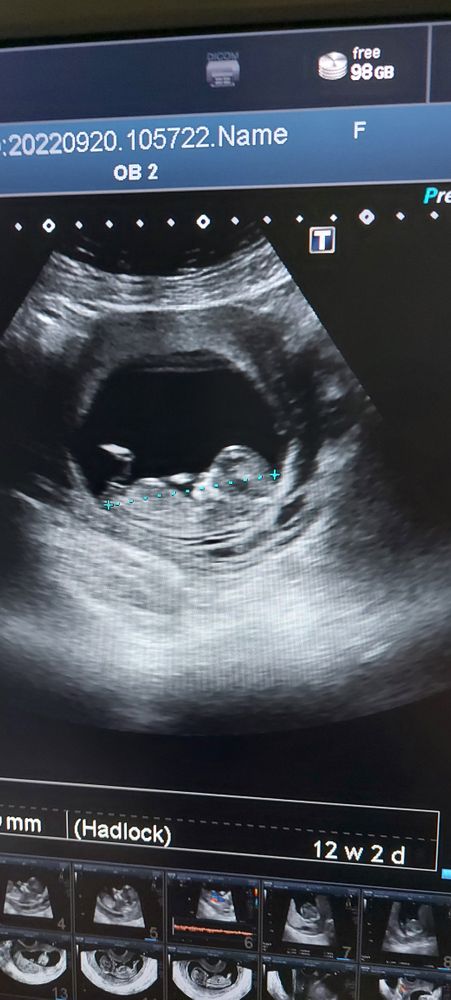

Определение пола по УЗИ

Девочка скорее, прям параллельно телу бугорок

Диана Ли, вот и мне кажется, что мальчик))) узист сказала, что очень не уверена, но думает, что девочка!) Прямо загадка какая-то)))))

Девочка, думаю, половой бугорок параллельно позвоночнику